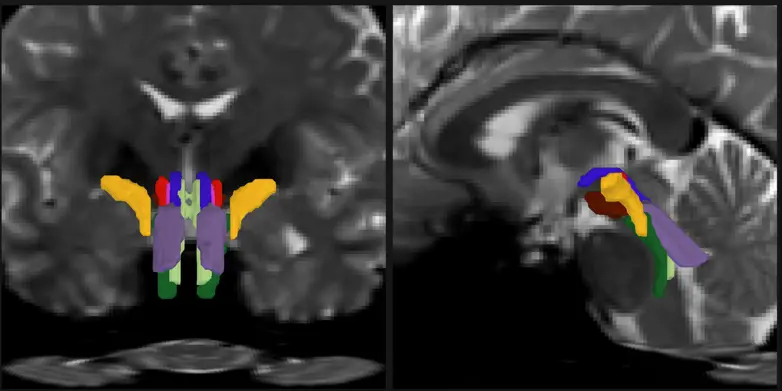

AI Algorithm Automatically Analyzes Brainstem White Matter Fiber Tracts